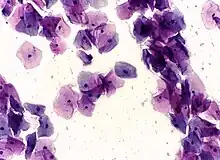

Normal squamous epithelial cells in premenopausal women

Atrophic squamous cells in postmenopausal women